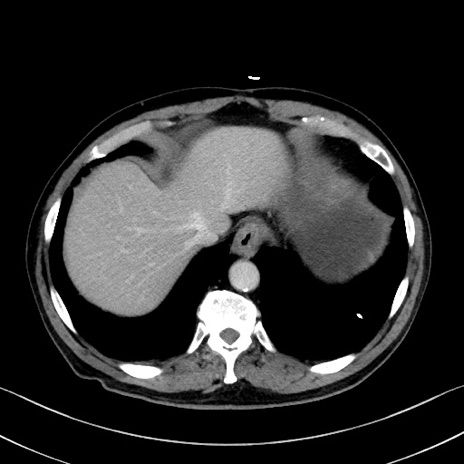

症例35(横断像)

【症例】70歳代 男性

【主訴】腹部膨満、嘔吐

【現病歴】昨日より腹部膨満感出現。本日増悪し、仙痛出現。嘔吐あり、受診。

【既往歴】糖尿病、胆摘後

【身体所見】BP 149/80mmHg、HR 74/min、BT 35.9℃、腹部:膨満、軟、圧痛なし。腸雑音減弱あり。上腹部正中切開瘢痕あり。

【データ】WBC 13500、CRP 1.72